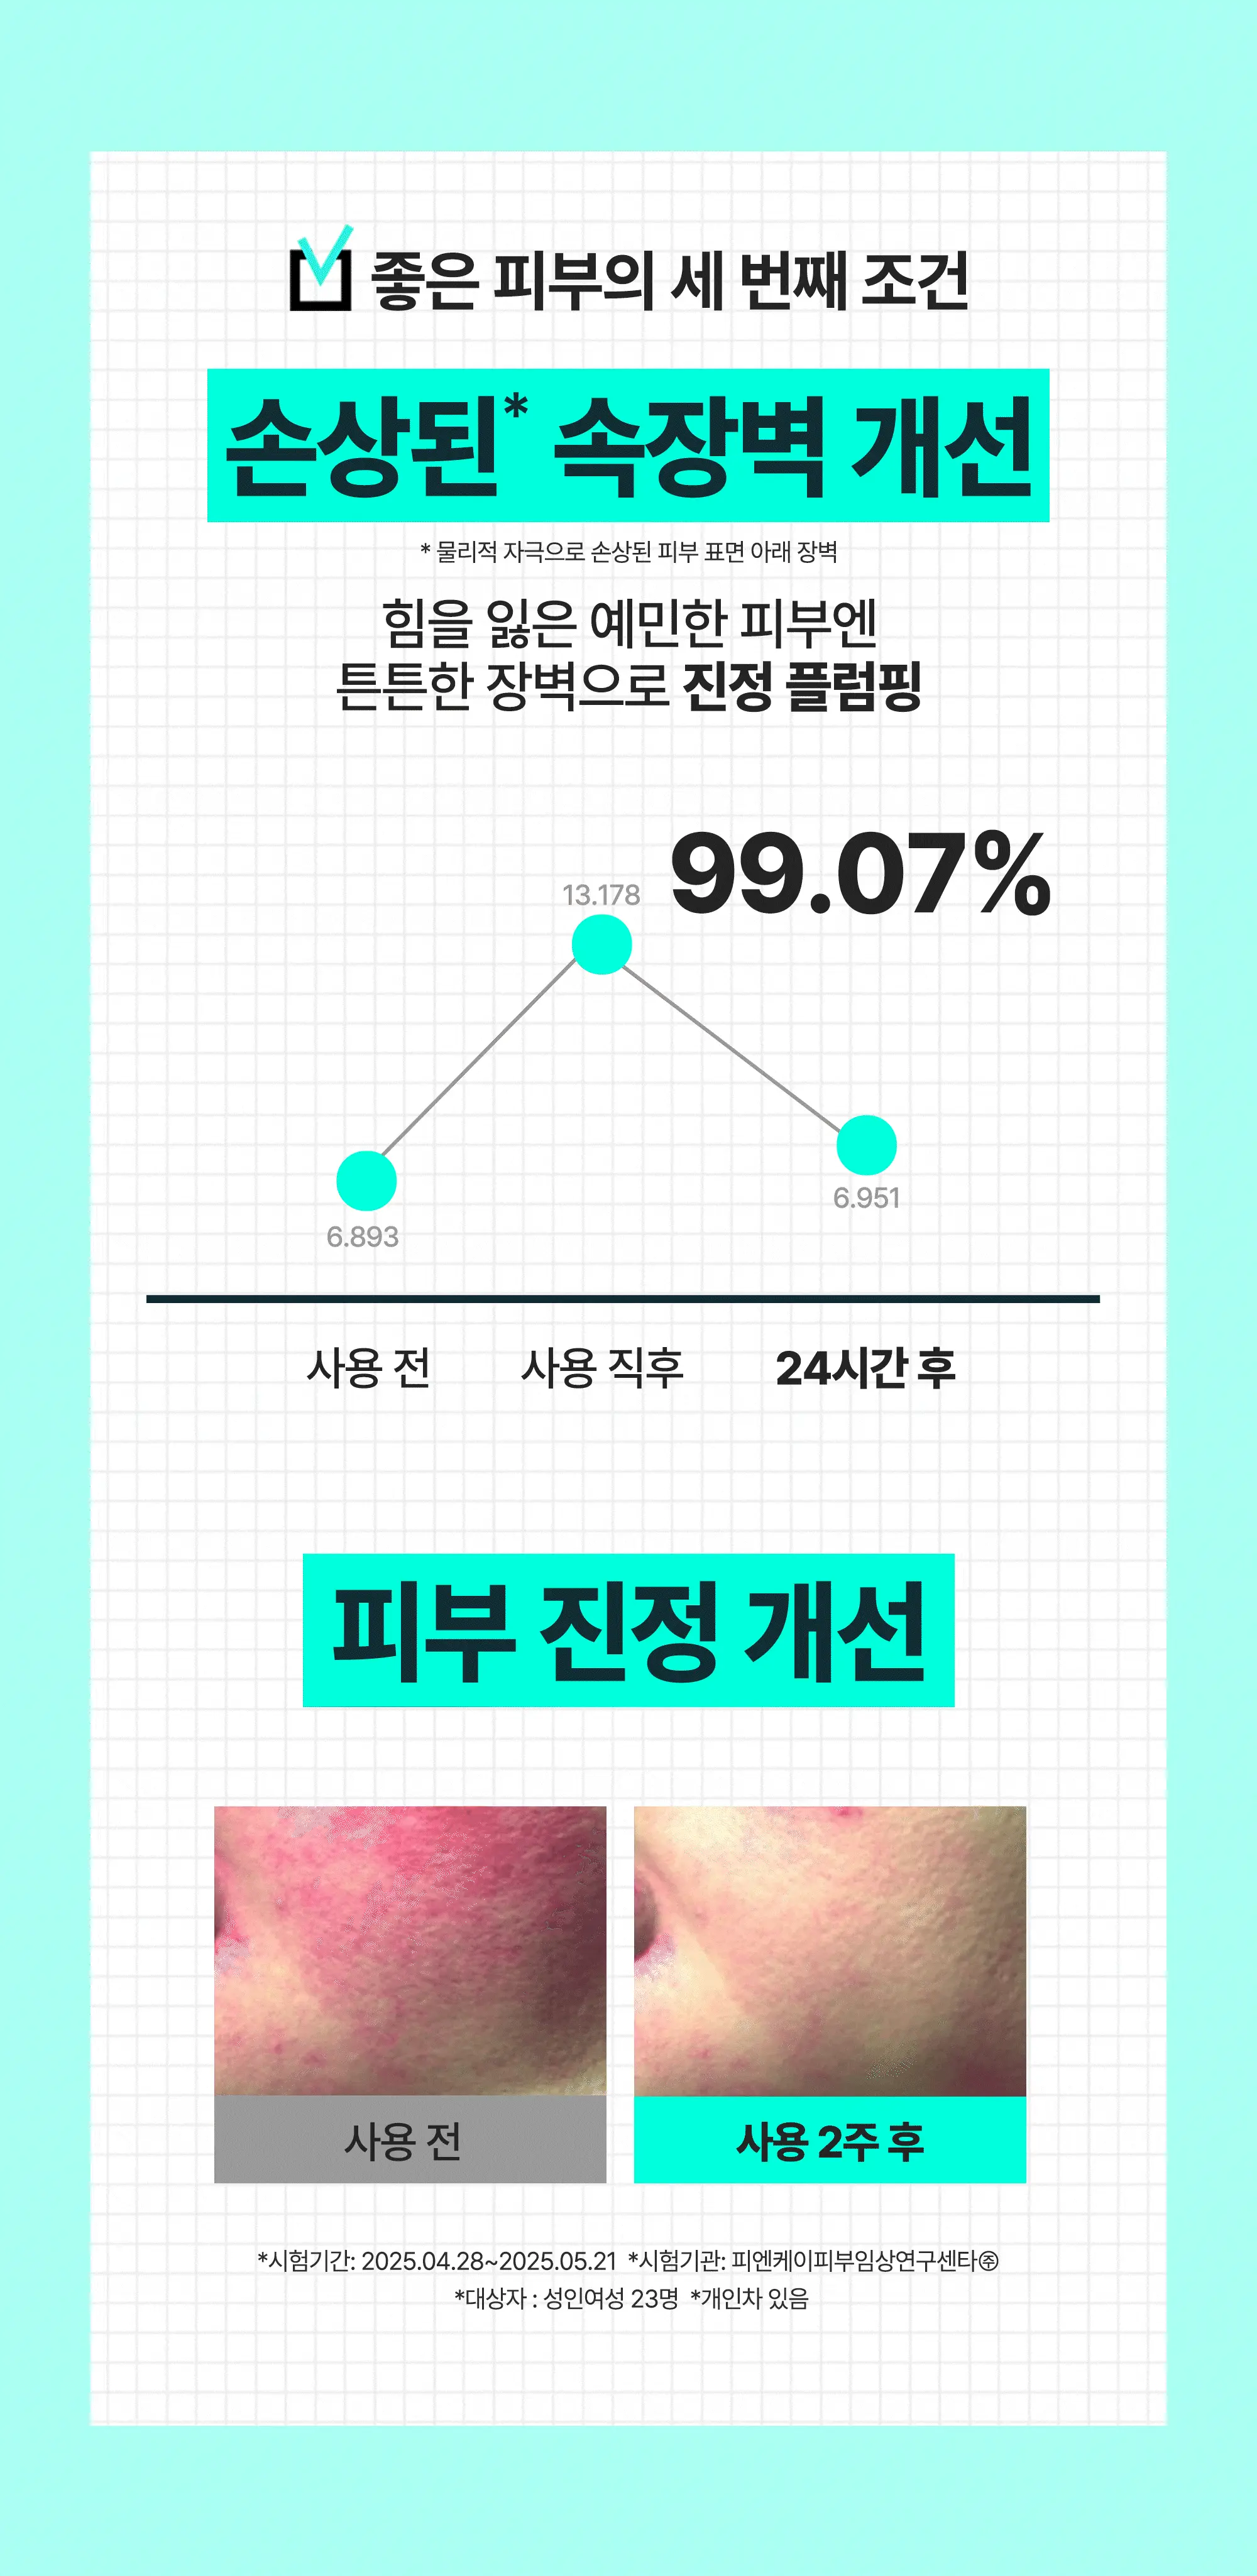

- 主打三大集中護理:光澤集中護理、彈力 Plumping、內在屏障修復(適合敏感肌)。

- 「皮膚 plumping(豐盈)效果之人體適用試驗」。

- 物理性刺激造成受損肌膚的即時(暫時)內在屏障改善」。